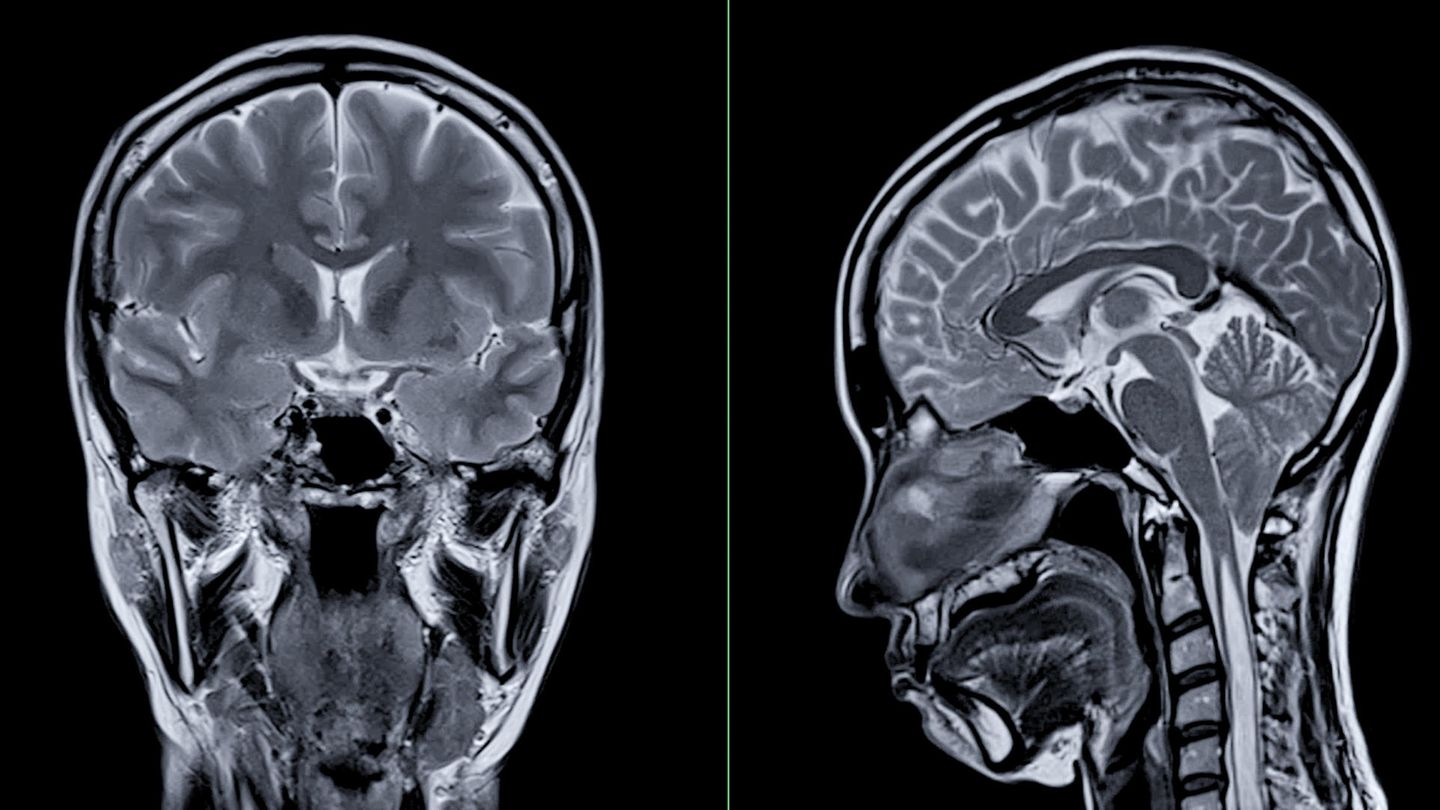

Hirnforschung: Studie zeigt auffällige Gehirn-Veränderungen bei Jugendlichen in der Pandemie In der Corona-Pandemie haben Jugendliche, vor allem aber Mädchen, einen übereilten Reifungsprozess ihres Gehirns durchgemacht, so das Ergebnis einer neuen Studie. Was das bedeutet. |

In der Corona-Pandemie haben Jugendliche, vor allem aber Mädchen, einen übereilten Reifungsprozess ihres Gehirns durchgemacht, so das Ergebnis einer neuen Studie. Was das bedeutet.